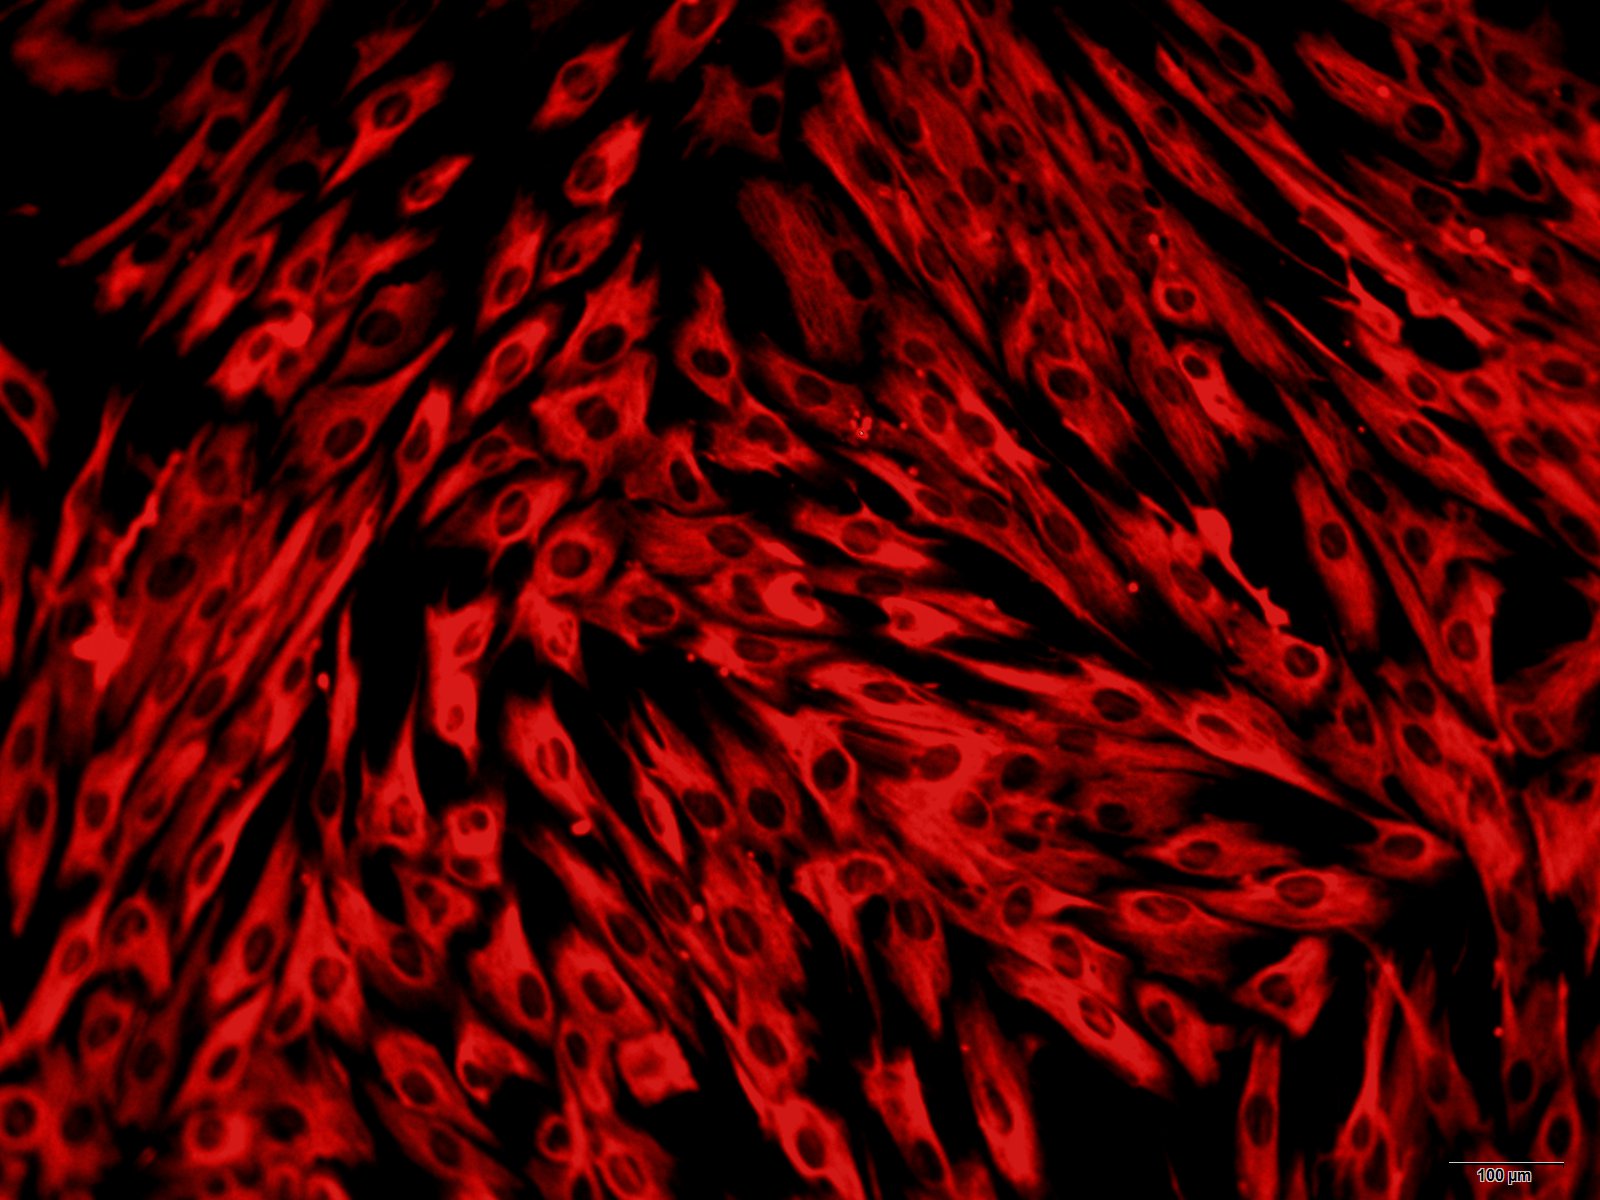

本公司生产的人脐带血干细胞采用密度梯度离心法制备而来,细胞总量约为5×105/T25方瓶,细胞纯度可达90%以上,且不含有HIV-1、 HBV、HCV、支原体、细菌、酵母和真菌等。

与细胞系相反,原代细胞是非常敏感的细胞,需要传统培养基之外的额外营养物质。为了优化原代细胞的存活和生长,需要针对每种细胞类型选择特定的培养基。例如,内皮细胞对营养的需求与上皮细胞或神经元有很大区别,因此需要特制的内皮细胞培养基。而传统的细胞培养基依靠血清提供生长因子、激素、脂质和其他的未知组分,以支持细胞的生长。但对于原代细胞,高血清水平可导致细胞分化,或促进污染细胞如成纤维细胞的生长。